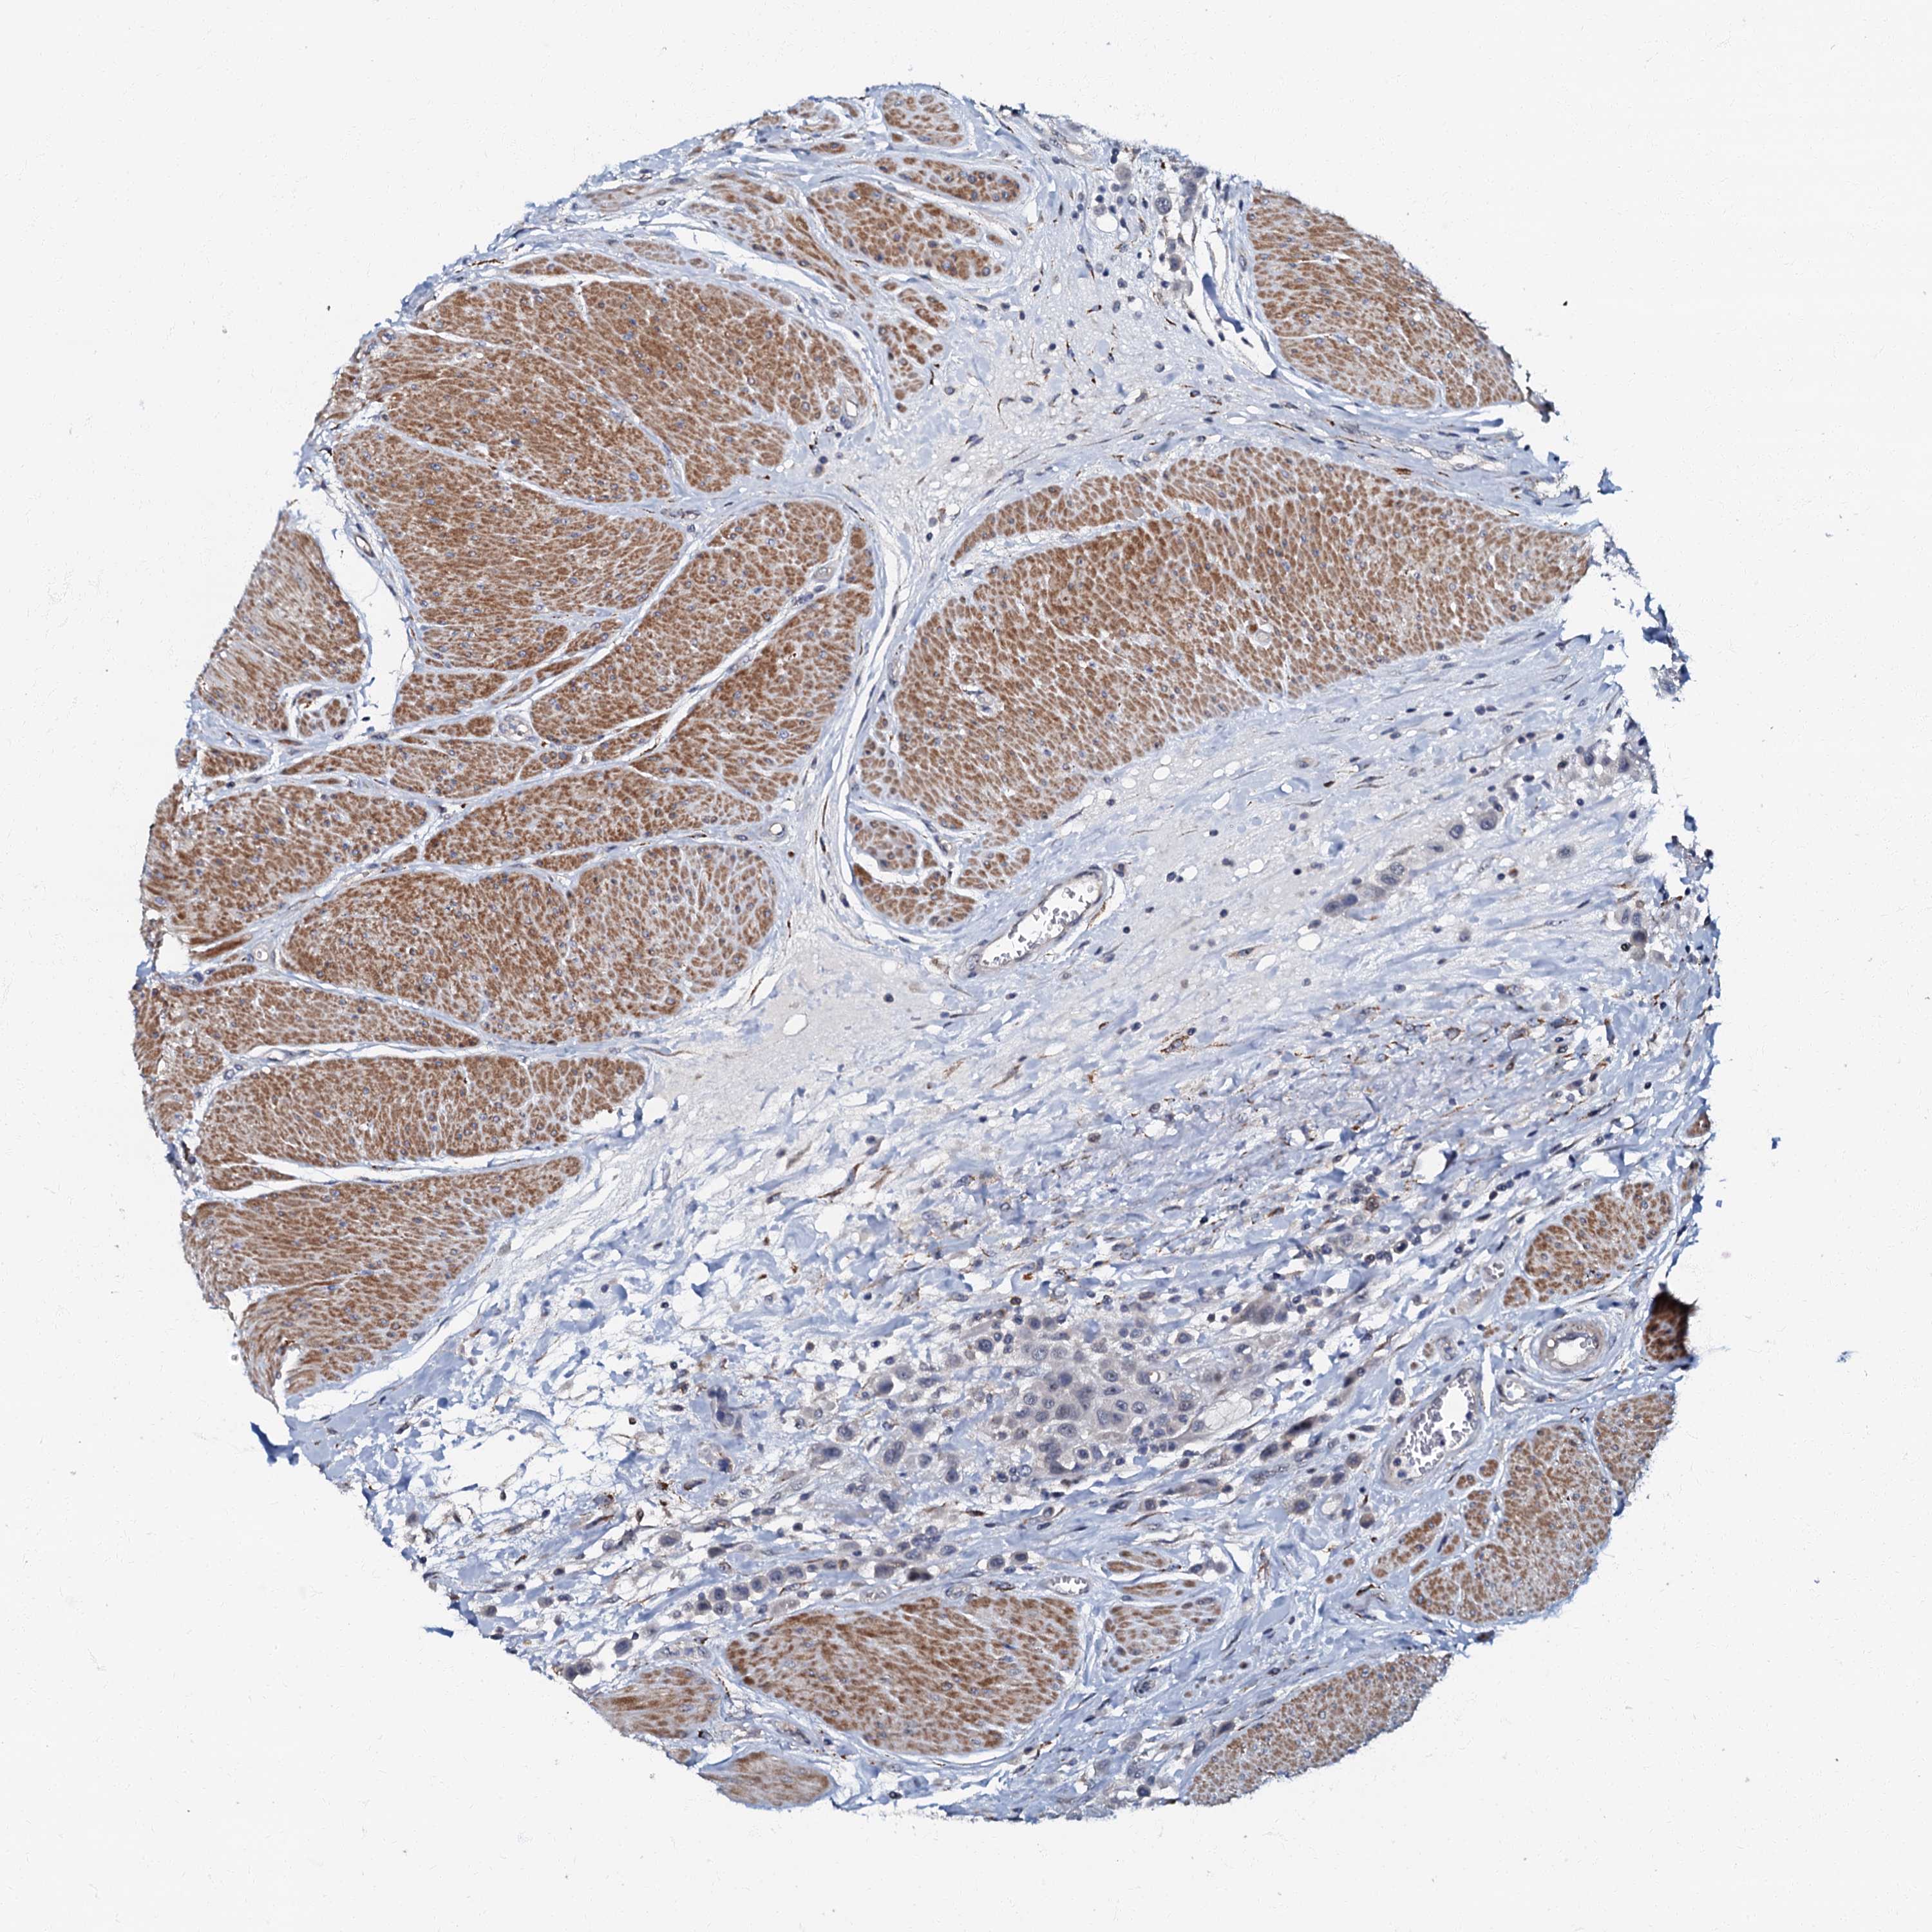

UROTHELIAL CANCER - Protein expressioni

A mouse-over function shows sample information and annotation data. Click on an image to view it in a full screen mode. Samples can be filtered based on level of antibody staining by selecting one or several of the following categories: high, medium, low and not detected. The assay and annotation is described here.

Note that samples used for immunohistochemistry by the Human Protein Atlas do not correspond to samples in the TCGA dataset.

Antibody stainingi

Antibody staining in the annotated cell types in the current human tissue is reported as not detected, low, medium, or high, based on conventional immunohistochemistry profiling in selected tissues. This score is based on the combination of the staining intensity and fraction of stained cells.

Each image is clickable and will lead to virtual microscopy that enables deeper exploration of all samples and also displays staining intensity scores, fraction scores and subcellular localization as well as patient and tissue information for each sample.

Antibody HPA037947

Antibody HPA037948

Staining

High

Medium

Low

Not detected

Intensity

Strong

Moderate

Weak

Negative

Quantity

>75%

75%-25%

<25%

None

Location

Nuclear

Cytoplasmic/membranous

Cytoplasmic/membranous,nuclear

Urothelial carcinoma, High grade

Urothelial carcinoma, Low grade

Urothelial carcinoma, NOS